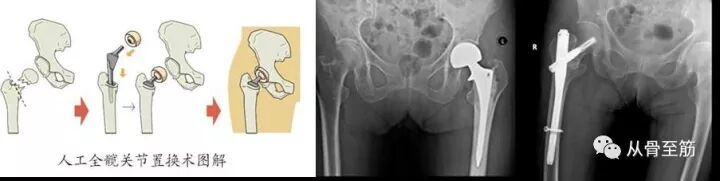

? ? 近年来,老人骨折后,接受外科手术的越来越多了。百岁老人手术已不是新闻。因为现在手术技术进步,换人工关节手术只需半小时到1小时,术后2-3天就能下床。微创内固定,手术时间也只需半小时到1小时左右,术后第二天就能坐起活动,也能早期下床活动。能极大减少并发症,减轻痛苦,提高了生活质量,也减轻了家人照料的负担。